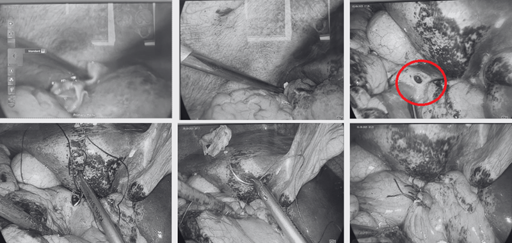

Phẫu thuật thay đổi giọng nói chính là cách phẫu thuật dây thanh quản khiến cho giọng nói của bạn trở nên trong trẻo và mềm mại hơn (nếu bạn là nữ). Ngược lại, với những trường hợp chuyển sang giới tính nam, phẫu thuật giọng nói chính là cách làm nhỏ dây thanh quản và làm ngắn dây thanh âm khiến bạn có chất giọng trầm ấm, thấp hơn bình thường.

Các bác sĩ sẽ phẫu thuật nhằm thay đổi những nếp gấp ở phần dây thanh âm để người phẫu thuật có chất giọng phù hợp hơn với ngoại hình của họ. Trước khi phẫu thuật, bệnh nhân sẽ được gây mê toàn thân. Thời gian phẫu thuật thường kéo dài khoảng 2 đến 3 giờ. Sau phẫu thuật, bệnh nhân cần ở lại viện khoảng vài ngày để được bác sĩ theo dõi chặt chẽ tình trạng sức khỏe.